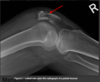

Dx

Tibial plateau fracture

Distal femur fracture

Cruciate or collateral ligament injury

Quadriceps tendon rupture

Plain film radiographs (AP, lateral and skyline) even if Skyline view is often not possible due to pain inhibiting knee flexion to the necessary 30 degrees

CT is indicated in comminuted fractures or if not seen on x-ray but clinical suspicion is there